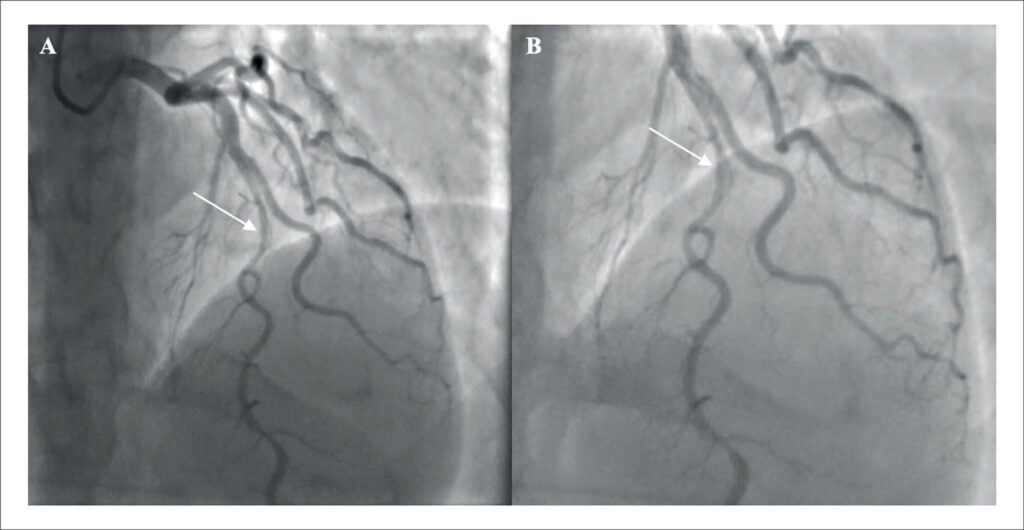

Dissecção de Artéria Coronária Após Ecocardiografia sob Estresse Farmacológico e o Seguimento do Tratamento Clínico: Um Relato de Caso

A dissecção espontânea da artéria coronária (DEAC) continua sendo um desafio diagnóstico e terapêutico na avaliação de dor torácica. A interpretação inadequada das características da dor, associada à falta de consideração do perfil epidemiológico do paciente, pode conduzir a abordagens diagnósticas e terapêuticas inadequadas. O caso descrito neste relato representa apenas o segundo caso com características semelhantes publicado em bases de dados médicas de grande relevância. Este relato enfatiza a importância de considerar causas incomuns de dor torácica e síndrome coronariana aguda (SCA), além de apresentar uma breve revisão da literatura pertinente. Este relato foi elaborado de acordo com as diretrizes CAse REport (CARE).